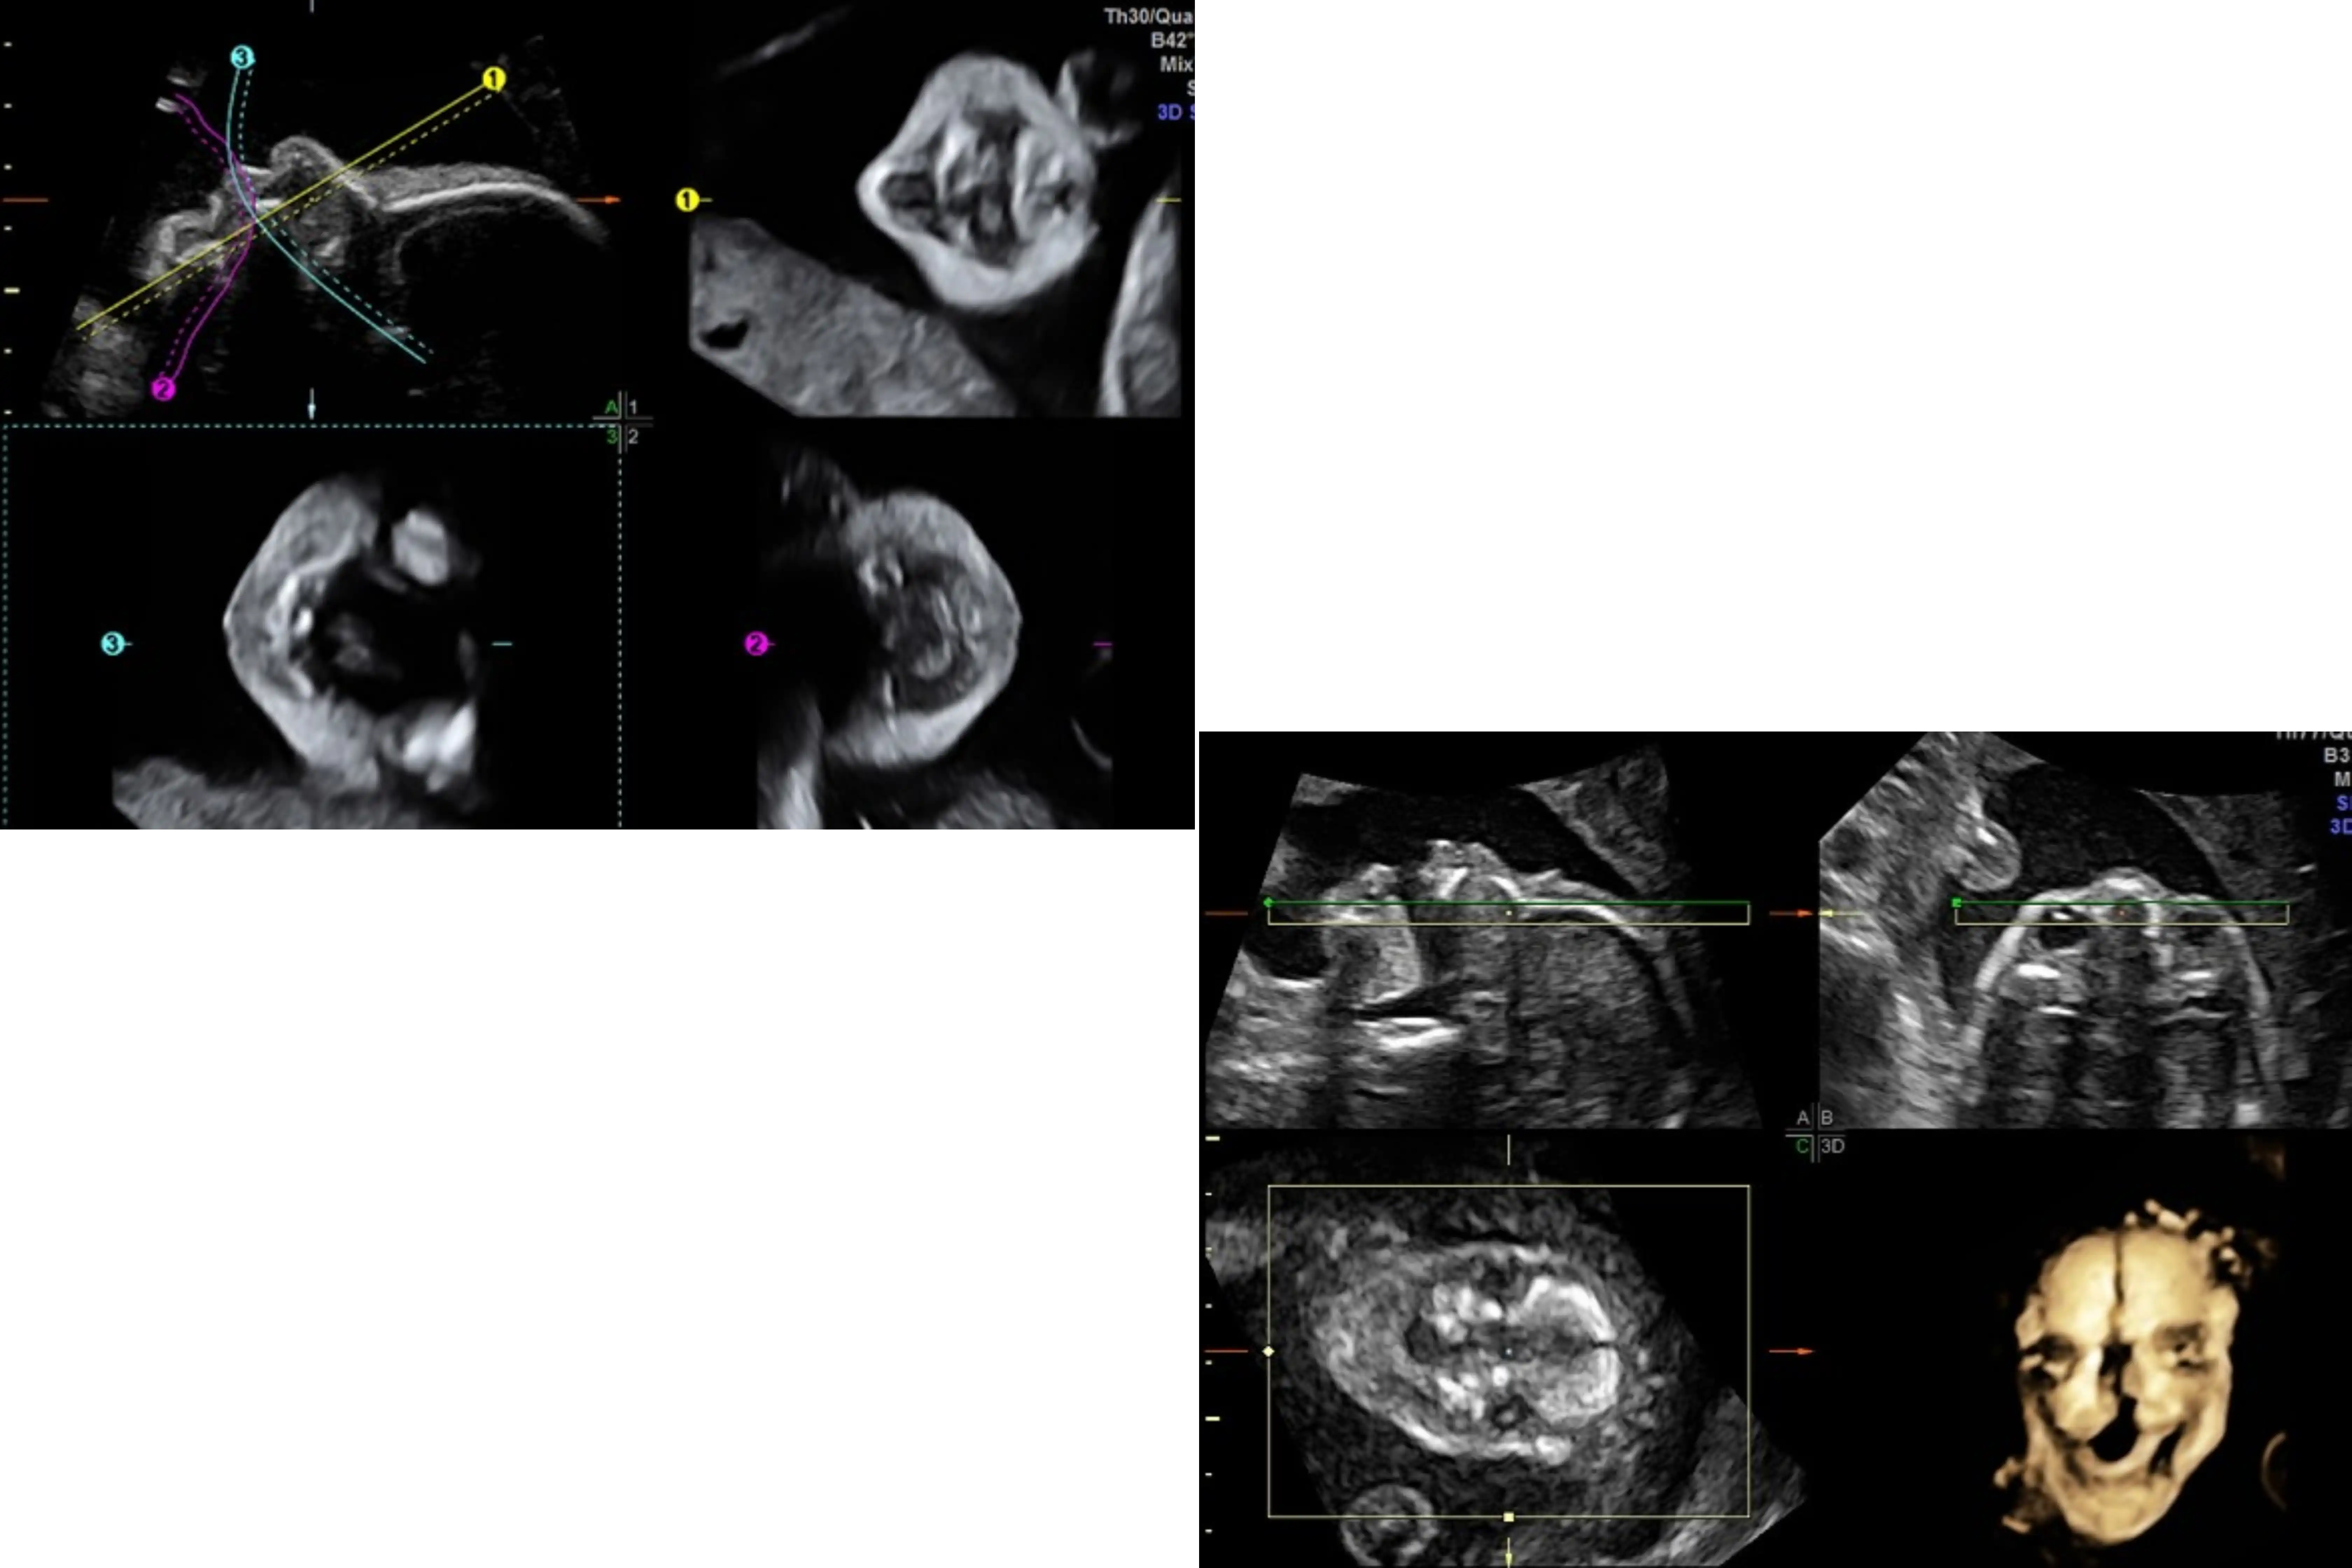

1c. Advanced 3D/4D workshop

Fetal Brain

Use of STIC - Cardiac 4D